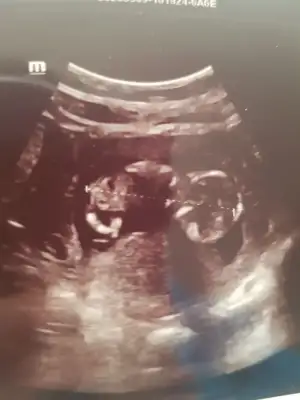

12+4..tahmininizi bekliyorum..

Eklentiler

• 20201022_181417.webp

20201022_181417.webp

32,1 KB · Görüntüleme: 91

• 20201023_150518.webp

20201023_150518.webp

34,4 KB · Görüntüleme: 80

• 20201023_150459.webp

20201023_150459.webp

40,8 KB · Görüntüleme: 79

Doktor erkek dedi ama 12.hafta olunca ben emin olamadım. Pipi fotosu da vermiş, ona da bakınca çok emin olamıyorum. Belli bir aya dek benzer gittiği için genital organlar, belki yanılmıştır diyorum..kız istediğim için..umarım bir ay sonra, yanılmışım, kızmış der doktor..